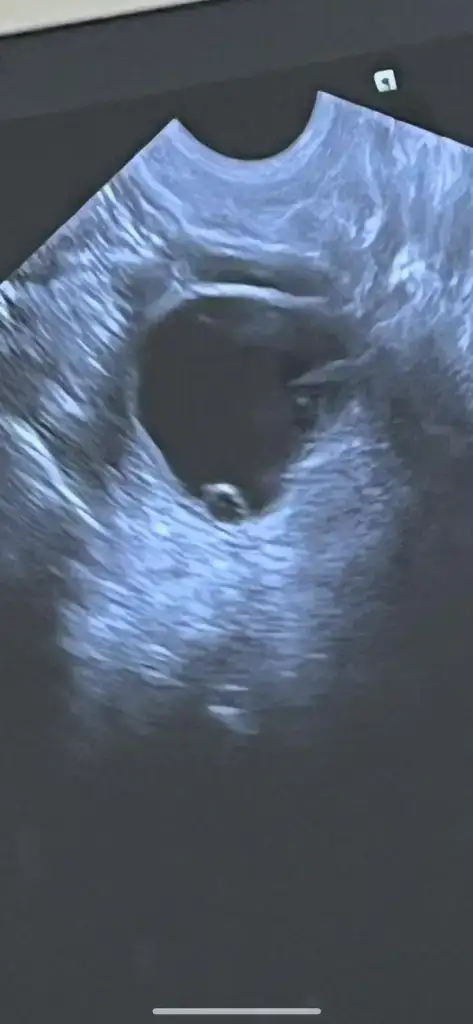

Kızlar selam. Yumurtlama sürecimi hiç takip etmediğim için maalesef bilmiyorum, bu konuda tecrübelerinize ve desteğinize ihtiyacım var. SAT 25 Şubat, 10 Mart'ta lekelenme ve ağrı başladı. Lekelenme ve ağrılar tam 16 gün sürdü, 25 Mart'ta bitti. Dayanılmayacak gibi değil fakat zaman zaman artan (ağrı kesiciye ihtiyaç duyulan), zaman zaman ise hafifleyen/kaybolan bel ve kasık ağrıları bu süre içinde hep devam etti. Reglden 14 gün sonra başladığı için yumurtlama olduğunu düşünüyorum. Ancak süre çok uzun geldi. Doktora gittim fakat net bir yorum yapamadı. Dış gebelik veya yumurtlama olduğunu düşünerek beta-hcg istedi. Pozitif çıkarsa tekrar gelirsin, negatif çıkarsa yumurtlamadır dedi. Sonuç negatif (2) çıktı, araya bayram da girince tekrar gidemedim. Henüz regl olmadım, reglimi hangi günden hesaplayacağımı da bilemiyorum. Sizce yumurtlayamama ya da yumurtamın çatlayamaması gibi bir durum olabilir mi? Veya dış gebelik, kimyasal gebelik tarzı bir şey? Benzer bir durum yaşayanınız oldu mu?

Ultrason görüntüsü de 17 Mart tarihine ait. Yani döngümün 21. günü. Belki USG ultrason görüntüsünden anlayan birileri çıkar :(

Eki Görüntüle 3569359